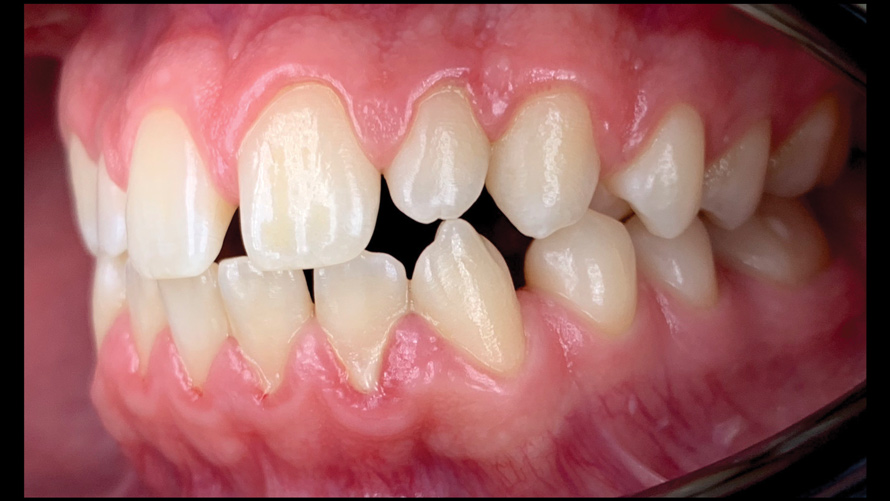

(9.) Preoperative esthetic case documentation using a smartphone and an EALS device.

Figure 9

(10.) Preoperative esthetic case documentation using a smartphone and an EALS device.

Figure 10

(11.) Preoperative esthetic case documentation using a smartphone and an EALS device.

Figure 11

(12.) Intraoral photographs taken with a smartphone and an EALS device for orthodontic evaluation.

Figure 12

(13.) Intraoral photographs taken with a smartphone and an EALS device for orthodontic evaluation.

Figure 13